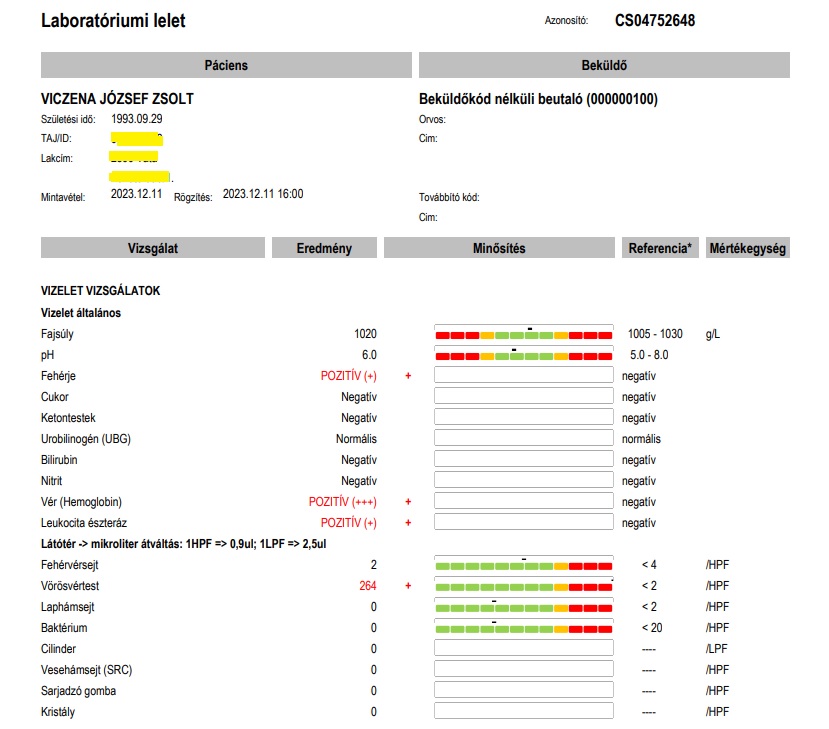

A vesekőzúzást (ESWL) tágult, gyulladt vesén végezték. Az operációnál, mert hogy ez annak számít, nem volt jelen az orvos! (De később a papírt kiküldte Dr Mosonyi Péter egy kolléganőjével az orvosi szobából, ekkor már operatőrként aláírva!) Ezért a technikus és a nővér tanácstalanok voltak, mit tegyenek egy ilyen gyulladt, tágult vesével, amit ultrahanggal láttak, elvégezzék-e a beavatkozást. Végül a kőzúzás mellett döntöttek. A fiam veséje az egyik legnagyobb mennyiséget, 3000-es ütésszámot kapta! Három hét múlva a fiam észrevette, hogy vérvizelése van. Odaadta az edényt, hogy vigyem le a háziorvosához, Dr Reisz Kornéliához, hogy adjon egy beutalót rá, hogy gyorsan le tudjuk adni. Megtagadta a beutalót, azt mondta, majd az asszisztens tesztcsíkkal megnézi. Aki pedig azt állapította meg, hogy „nincs benne vér, picike fehérje, de vér nincs.” A fiam otthon felrobbant a hülyének nézéstől, felöltözött és a már akkor is rossz állapotában maga vitte el a tatabányai Synlab-hoz leadni ugyanezt a vizeletet. A „nincs vér” igazából 3 keresztes vérvizelés és 100-szoros vörösvörtest/látótér volt. Már ekkor elkezdődött az, amiből aztán ahogy a cikk címe is utal rá, egy horrortörténet lett!

Február 8-án leadtuk a véres a vizeletet, melynek eredményét úgy kellett telefonon kikérni, szinte alig adták ki, mert olyan brutális, ezerszeres vérvizelés értékeket (2124 illetve 1286 vörösvértest/látótér) jelzett a vizsgálat, amilyennel szinte nem találkoztak, magánbeteg által leadott mintáknál szinte biztosan nem – mert aki ilyen beteg egyből állami kórházi ellátást kap civilizált országokban. A normális tartomány határa 2 vörösvértest látóterenként, a vizsgálat pedig vér+++, proteinuria ++, ketonuria +, leukocyta észteráz + értékeket mutatott. A Synlab az egyetlen megbízható pont volt számunkra, amely rengeteg vizeletvizsgálatot és egyéb labormunkákat végzett nekünk, rengeteg pénzt kellett otthagynunk.